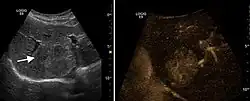

They can be single or multiple, with variable size, generally less than 20 mm (congenital). Rarely, sizes can reach several centimeters, leading up to the substitution of a whole liver lobe (acquired, parasitic). They may be associated with renal cysts; in this case the disease has a hereditary, autosomal dominant transmission (von Hippel Lindau disease).

The ultrasound appearance is a well defined lesion, with very thin, almost unapparent walls, without circulatory signal at Doppler or CEUS investigation. The content is transonic suggesting fluid composition. The presence of membranes, abundant sediment or cysts inside is suggestive for parasitic, hydatid nature. Posterior from the lesion the acoustic enhancement phenomenon is seen, which strengthens the suspicion of fluid mass. They typically displace normal liver vessels but no vascular or biliary invasion occurs.

- Liver cyst

- Hydatid liver cyst. Diagnostic criteria are the presence of membranes and sediment inside.